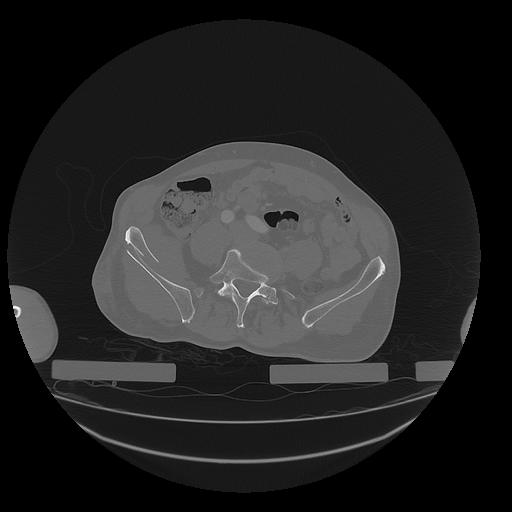

31 PULMON,CE,Vol,1.0,PULMON,,